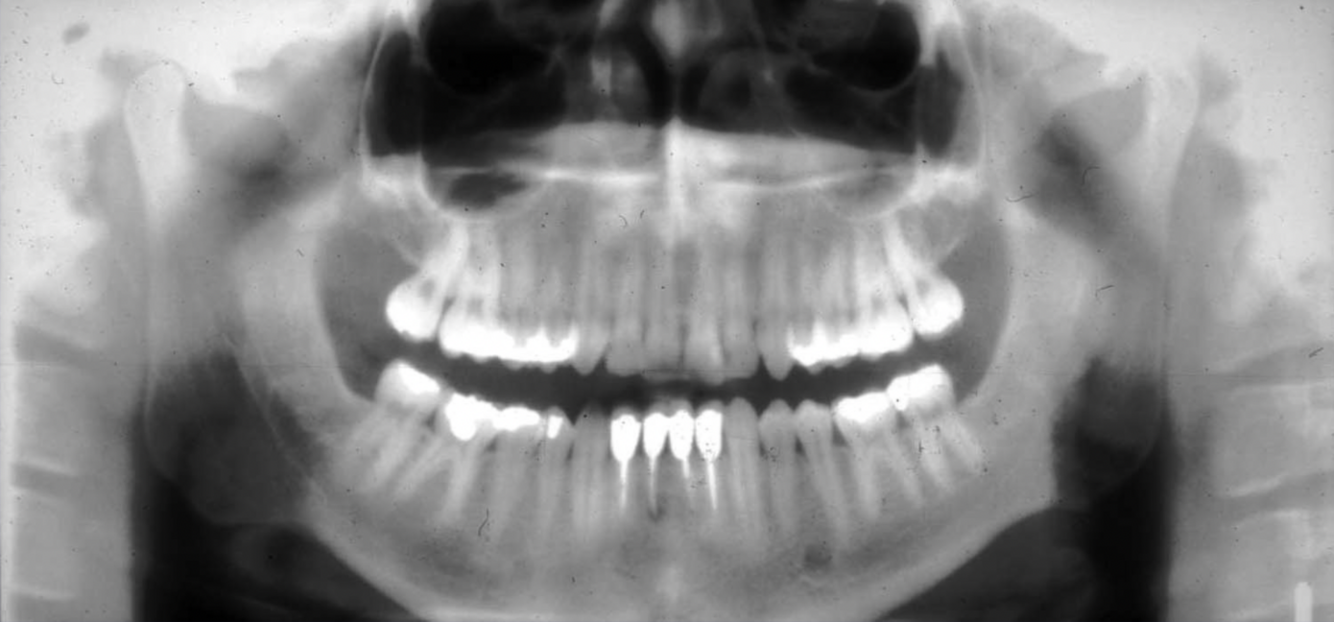

What are some errors that can be seen in this radiograph? What is the cause?

1. flat occlusal plane or reverse curvature 2. roots of maxillary anterior teeth are blurred 3. rami/condyles tipped laterally 4. condyles close to or cut off the side of image 5. hard palate superimposed on maxillary apices cause: chin up